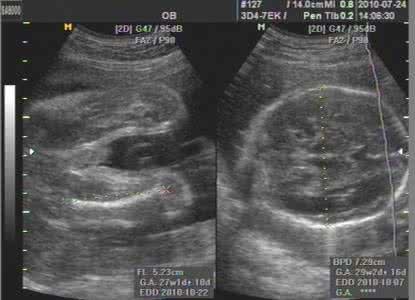

第三次B超:在怀孕18~24周时,主要是系统筛查胎儿发育及诊断胎儿致命性畸形。

此次超声检查尤为重要,因为,胎儿发育至这个时期,胎儿在子宫内所占的空间不太多,活动的空间较大,胎儿的活动较为舒展,超声可以通过多个观察角度观察到胎儿大部分的器官形态结构,筛查排除胎儿畸形。此时也可确定怀的是单胎还是多胎,并可测量胎儿头围等。